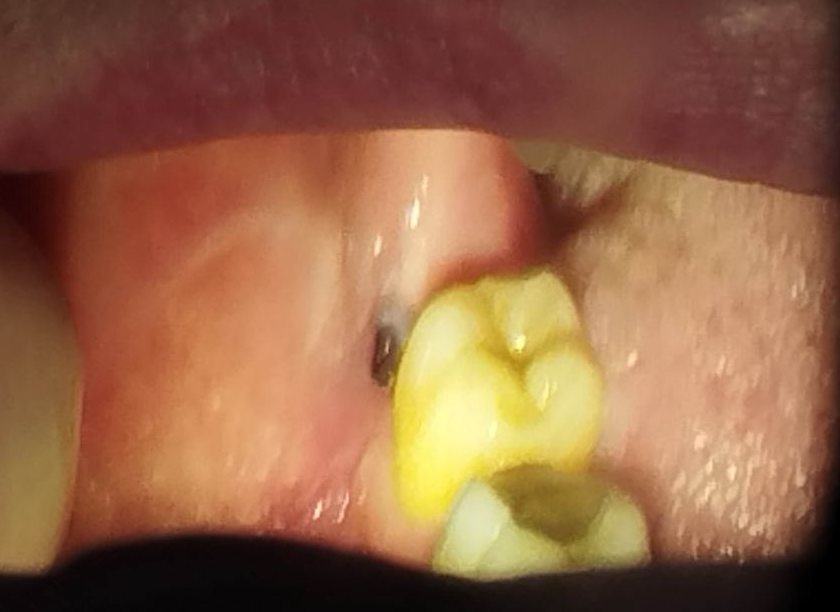

3убастик Опубликовано 27 мая, 2023 Поделиться Опубликовано 27 мая, 2023 Здравствуйте, подскажите как быть. Удалили сложную ретинированную восьмерку снизу, по причине что начала гноиться десна, зуб был в порядке. 10 дней лунка обрабатывалась ванночками из хлоргексидина после еды и еще несколько раз в промежутках. Спустя 10 дней, поняв что лунка не заживает, 10 дней в лунку закладывался левомеколь 3 раза в день на 20 минут на кусочке бинта (сам себе назначил по советам из интернета), убедившись что ничего не меняется на 23 день после удаления пошел к врачу, где был обнаружен небольшой альвеолит. Лунка была промыта хлоргексидином, врач вымыл остаток кровяного сгустка, назначил асепту, которая закладывалась в лунку по 2-3 раза в день. Через 3 дня был повторный осмотр с промыванием лунки, она оказалась чистой, продолжил закладывать асепту (14 дней), лунка особо не заживает до сих пор (сегодня 38 дней после операции и 15 дней как закладываю асепту), сделал повторный снимок, сходил еще раз на осмотр, врач сказал что стало немного получше, кюретаж не требуется, предложил продолжить до месяца использовать асепту и ждать пока затянется. В последние пару дней пару раз после закладывания асепты щипало в лунке минут по 10-15, до этого не было такого. Другой хирург посоветовал закладывать солкосерил, но меня смущает что через это лекарство может передаться болезнь Крейтцфельда-Якоба, которая аукнуться может через 5-15 лет и закончиться очень плачевно, плюс сам солкосерил сейчас стоит космических денег - за 5 г. тубу около 5 тысяч рублей. Подскажите, стоит ли использовать солкосерил, или может есть какие-то безопасные препараты для ускорения эпителизации? Прикладываю снимки до и после, плюс фото самой лунки, может кто на снимках что увидит почему не затягивается. И еще вопрос, на 7 зубе это что за вмятинка, отметил стрелкой на фото? Не может быть повреждения во время операции? Сверлили много... До удаления: После удаления: Лунка: Ссылка на комментарий

3убастик Опубликовано 9 июня, 2023 Автор Поделиться Опубликовано 9 июня, 2023 27.05.2023 в 21:28, Irouil сказал: Нормально Поделал по вашей схеме. Завтра утром будет как 2 недели закладывал 2 раза в день на 15 минут метрогил, промывал раза 3 после еды хлоргексидином, сейчас лунка выглядит таким образом. Есть чувствительность к горячему\холодному. Подскажите, это нормальное состояние? И белый налёт внутри это фибрин? Что можно еще поделать чтобы поскорей зажило, метрогил я так понимаю уже не стоит продолжать, как и хлоргексидин. Ссылка на комментарий